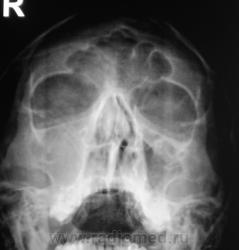

Пол пациента: Мужской пол Тип патологии: Другое Область исследования: Челюстно-лицевая область и шея Методы исследования: Rg Пациент направлен на рентгенографию придаточных полостей носа. Ваше мнение? https://radiomed.ru/sites/default/files/styles/case_slider_image/public/user/12/2..p8170059a.jpg?itok=7t4Nbh2k https://radiomed.ru/sites/default/files/styles/case_slider_image/public/user/12/3..p8170060.jpg?itok=IP4zEUbV https://radiomed.ru/sites/default/files/styles/case_slider_image/public/user/12/4..p8170060a.jpg?itok=H9fhfdKZ ID:5520 Ср, 18/08/2010 - 14:56 #1 Vikkur Не на сайте Был на сайте: 4 года 7 месяцев назад Зарегистрирован: 24.09.2009 - 14:34 Публикации: 1749 Мне видиться гиперпластический риносинуит, искривление носовой перегородки. причем спава практически тотальное затемнение.. Виктор. Ср, 18/08/2010 - 16:31 #2 Катенёв Валенти... Не на сайте Был на сайте: 7 лет 2 недели назад Зарегистрирован: 22.03.2008 - 22:15 Публикации: 54876 А, что по поводу нижнего края правой орбиты? У меня, что-то возникали сомнения, в "дефектности" этого контура. Ср, 18/08/2010 - 16:48 #3 Vikkur Не на сайте Был на сайте: 4 года 7 месяцев назад Зарегистрирован: 24.09.2009 - 14:34 Публикации: 1749 А есть ЛТ, потому что, я к своему стыду не вижу... Виктор. Ср, 18/08/2010 - 17:17 #4 Катенёв Валенти... Не на сайте Был на сайте: 7 лет 2 недели назад Зарегистрирован: 22.03.2008 - 22:15 Публикации: 54876 Есть. Сейчас выставлю. Ср, 18/08/2010 - 17:19 #5 Катенёв Валенти... Не на сайте Был на сайте: 7 лет 2 недели назад Зарегистрирован: 22.03.2008 - 22:15 Публикации: 54876 1 срез. Приложения: Ср, 18/08/2010 - 17:23 #6 Катенёв Валенти... Не на сайте Был на сайте: 7 лет 2 недели назад Зарегистрирован: 22.03.2008 - 22:15 Публикации: 54876 2 срез. Приложения: Ср, 18/08/2010 - 22:32 #7 Юрич Не на сайте Был на сайте: 6 лет 5 месяцев назад Зарегистрирован: 17.01.2010 - 09:55 Публикации: 351 я не вижу четко стенок в.челюстной пазухи справа - атрфия от давления? может мукоцеле? Чт, 19/08/2010 - 10:24 #8 Vikkur Не на сайте Был на сайте: 4 года 7 месяцев назад Зарегистрирован: 24.09.2009 - 14:34 Публикации: 1749 ассиметрия есть.. Виктор.

Мне видиться гиперпластический риносинуит, искривление носовой перегородки. причем спава практически тотальное затемнение..

А, что по поводу нижнего края правой орбиты? У меня, что-то возникали сомнения, в "дефектности" этого контура.

я не вижу четко стенок в.челюстной пазухи справа - атрфия от давления? может мукоцеле?